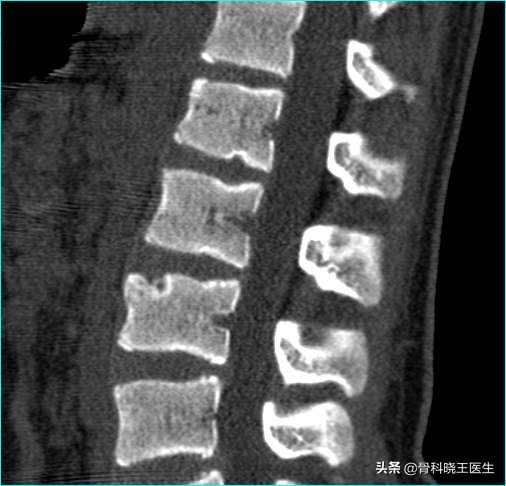

拿到一张CT或者核磁检查报告单,往往报告上会写着“腰椎间盘膨出”或者“腰椎间盘突出”,那么膨出和突出有什么不同呢?到底哪种严重?

简单来说,椎间盘由周围的纤维环和中央的髓核组成,在椎间盘的前方有前纵韧带,后方有后纵韧带,以此为基础,根据腰椎间盘突出症突出程度和影像学特征,可以分为5型,膨出和突出只是其中的两型,除此之外还有脱出型、游离型和Schmorl结节及经骨突出型。

腰突主要只髓核突出,分为5型

- 膨出型 纤维环有部分破裂,但表层完整,此时髓核因压力向椎管内局限性隆起,但表面光滑。这一类型保守治疗大多可缓解或治愈;

- 突出型 纤维环完全破裂,髓核突向椎管,但后纵韧带仍然完整。此型常需手术治疗;

- 脱出型 髓核穿破后纵韧带,形同菜花状,但其根部仍然在椎间隙内。需手术治疗;

- 游离型 大块髓核组织穿破纤维环和后纵韧带,完全突入椎管,与原间盘脱离。需手术治疗;

- Schmorl结节及经骨突出型 前者指髓核经上下软骨板的发育性或后天性裂隙突入椎体松质骨内;后者是髓核沿椎体软骨终板和椎体之间的血管通道向前纵韧带方向突出,形成椎体前缘的游离骨块。这两型临床上无神经症状,无需手术治疗。

Schmorl结节指髓核经上下软骨板的裂隙突入椎体松质骨内,无需手术治疗

从膨出型一直到游离型,病情逐渐加重,膨出型和Schmorl结节及经骨突出型通过保守治疗多无需手术,但是突出型、脱出型和游离型常需手术治疗。